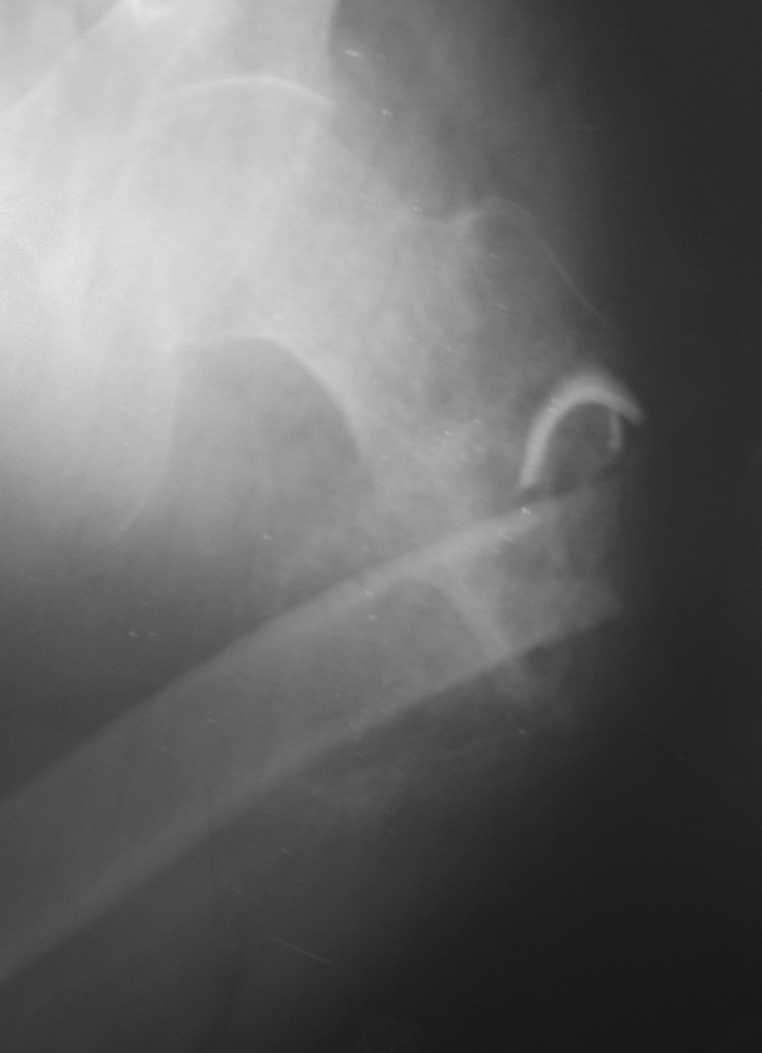

[Ortho] Неправильно консолидирующийся перелом бедра

Имя     : Изображение 024!.jpg